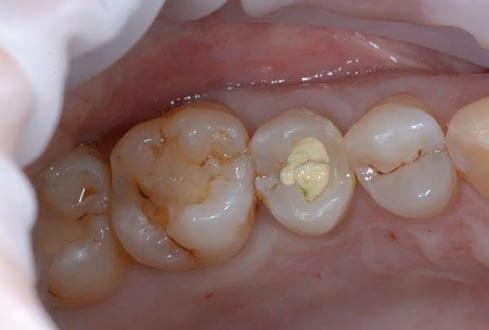

Figure 1: Initial situation. The patient reported generic pain in the second quadrant, where there was a restoration in temporary material on tooth number 25. Figure 2: Initial radiograph showing endodontic dressing that had been present for some months, but the treatment was never completed. Note the depth of the caries lesion and the proximity of the interdental bone ridge, which may represent an obstacle for prosthetic rehabilitation.

During the clinical oral examination, she didn’t exhibit any mucosal lesions, she presented an optimal level of oral hygiene but there were a lot of incongruous restorations and an apparently provisional restoration on tooth #25.

This element was not stimulated with the cold test and the radiographic image revealed an incomplete endodontic treatment (Figs. 1-2). The element seemed to present a suitable root length for a conservative restoration, but the apical position of the carious lesion and the proximity of the interdental bone ridge didn’t allow a correct rehabilitation with prosthetic crown, respecting the biological width.2